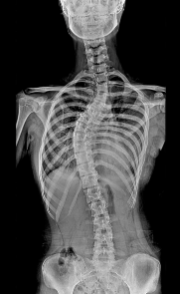

척추 측만증 증상 원인 치료방법 등 척추 측만증과 관련된 정보를 알아보도록 하겠습니다. 척추측만증은 척추의 관절 연골과 뼈가 마모되어 생기는 질환으로, 허리와 목 부위에서 가장 흔하게 발생합니다. 나이가 들면서 발생하는 질환으로, 디스크의 압력이 증가되거나 관절연골에 마모가 발생해 척추의 안정성이 떨어지게 됩니다. 이로 인해 허리나 목이 뻐근하고 아프게 느껴지며, 심한 경우는 근육 약화와 마비 등의 증상을 보일 수 있습니다. 척추측만증은 노화에 따라 발생하는 질환으로, 운동이나 근력강화 운동 등을 통해 예방할 수 있습니다.

보존적 치료는 척추 측만증이 심하지 않거나 성장기에 있는 환자에게 적용되는 방법입니다. 보존적 치료에는 물리치료, 근력운동, 자세교정, 브레이스 착용 등이 있습니다. 이러한 방법들은 척추 측만증의 진행을 막거나 완화하는 데 도움이 될 수 있습니다. 보존적 치료를 받는 환자는 정기적으로 의사와 상담하고, X-선 검사를 통해 척추의 상태를 모니터링해야 합니다.